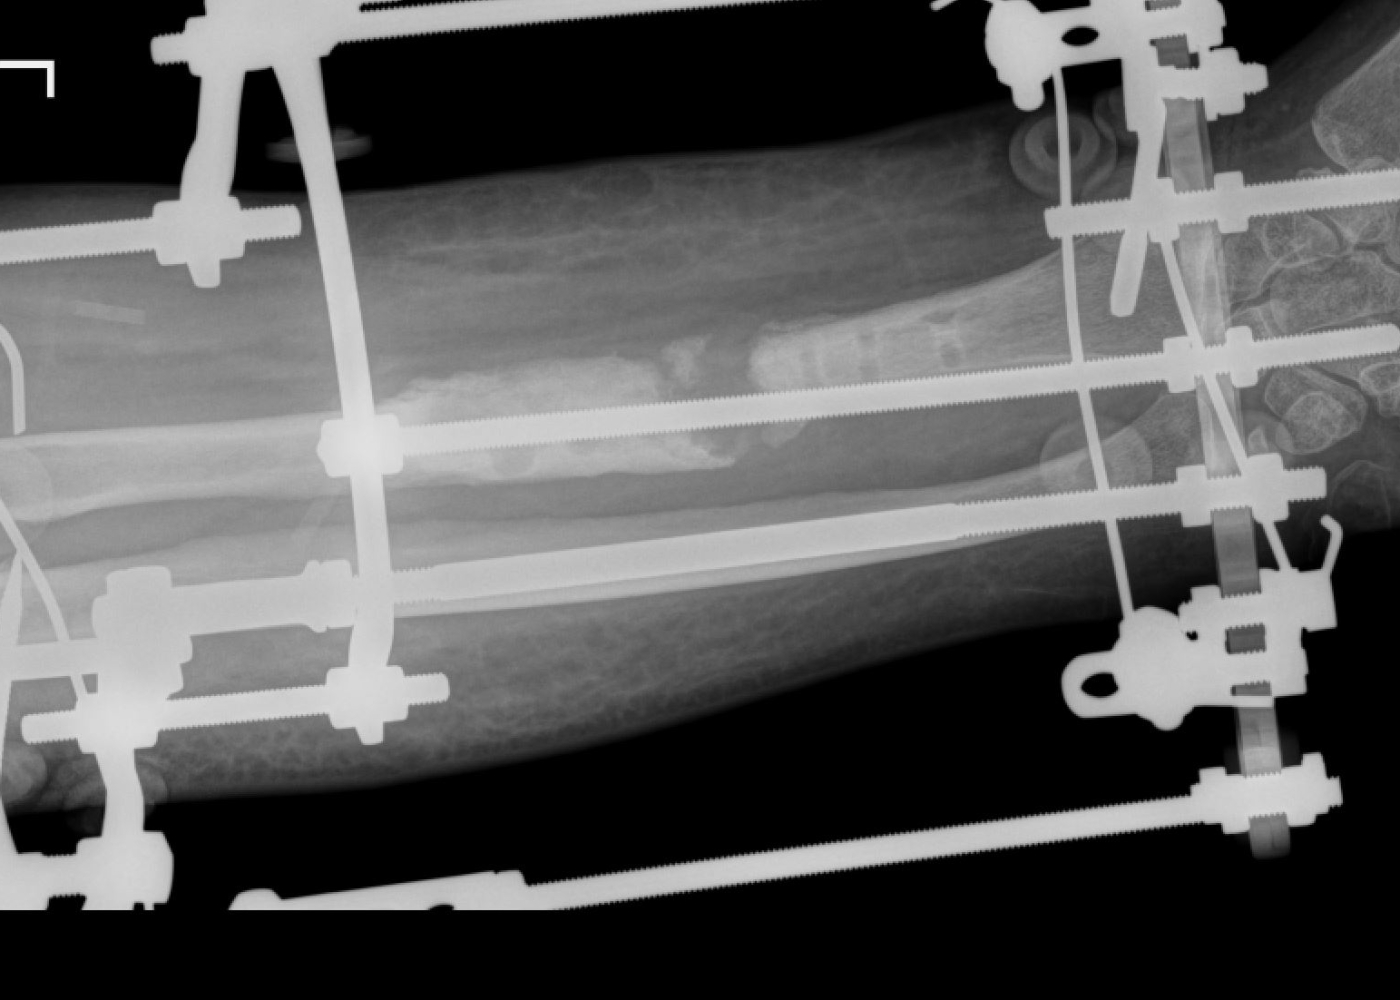

Որոշվել է վիրաբուժական ռազմավարությունը՝ բաղկացած երկու փուլից։ Առաջին փուլով Օրթոպեդիայի և վնասվածքաբանության բաժանմունքի վարիչ Սեյրան Սարոյանի կողմից կատարվել է ձախ նախաբազկի երկարեցում Իլիզարովի ապարատով, որը միտում ուներ նախ շտկել նախաբազկի կարճացման հետևանքով առաջացած հոդախախտը, ապա ապահովել փոքրացած և կարկամված մկանների և ջլերի էտապային, դանդաղ, անցավ երկարացումը։ Առաջին վիրահատության արդյունքում բուժառուի նախաբազուկը հաջողվել է երկարացնել մոտ 4 սմ-ով։

Երկրորդ վիրահատությամբ Միկրովիրաբուժության ծառայության ղեկավար Արթուր Մամբրեյանի և բժիշկ Սուրեն Թոփլաղալցյանի կողմից սրունքից վերցվել է ոսկրային տրանսպլանտանտ իր զարկերակով, որը միացվել է նախաբազկի զարկերակին։

Միաժամանակ, Օրթոպեդիայի և վնասվածքաբանության ծառայության ղեկավար Ատոմ Տեր-Գրիգորյանի, բժիշկներ Տիգրան Կուպալյանի և Խաչատուր Հարությունյանի կողմից կատարվել է ճաճանչոսկրի օստեոսինթեզ՝ մետաղական հատուկ հարթակի և պտուտակների օգնությամբ, որի վրա ֆիքսվել է ոսկրային դեֆեկտի հատվածում տեղադրված տրանսպլանտանտը։